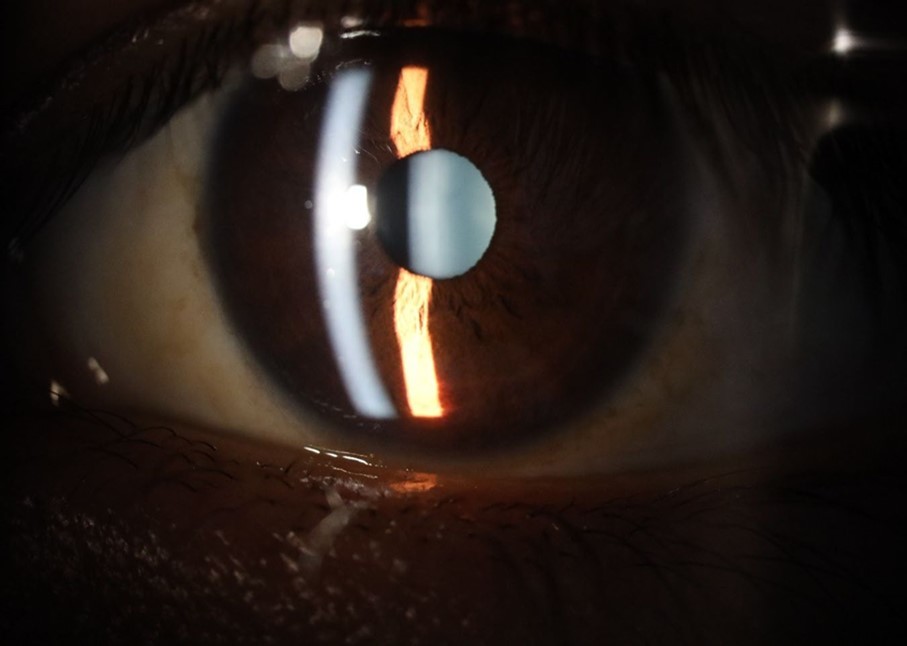

Figure 5.The slit-lamp photograph shows the anterior segment, relatively unscathed, in terms of transparent media (Cornea, crystalline and vitreous).

Figure 15.The photograph shows better specular reflection, compared to the first day of the exam.

Figure 16.The anterior segment of the right eye shows the vitreous with greater transparency. The cornea and lens, as well as the anterior chamber, are in good condition.

Figure 20.The mirror reflection of the affected (right) eye continues to improve.

Figure 25.Mirror reflection of the affected eye (right side), with good appearance. This indicates that the transparent media of the eyeball (Cornea, anterior chamber, lens, and vitreous) are in good condition.

Figure 26.The macrograph of the anterior segment of the right eye (affected) shows very good transparency of the cornea, anterior chamber, lens, and vitreous.